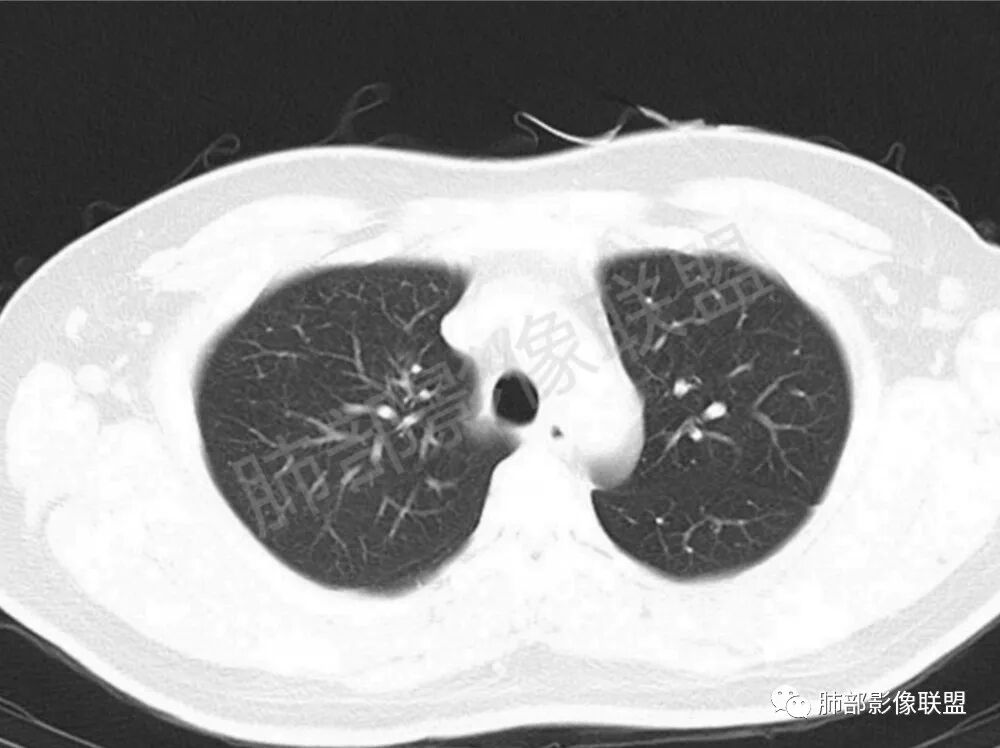

男性,22岁,HIV病史,症状半年,双肺多发大小不等结节影,边缘光滑,密度均匀,以胸膜下分布为主,部分与胸膜相连,胸膜下脂肪间隙可见,病灶近段支气管走行病灶内,远端似有堵塞,无增强图像,考虑隐球菌,鉴别:淋巴瘤,GPA

双肺多发结节影,膨隆,边缘光滑,圆顿,沿支气管血管束分布为主,部分贴胸膜,部分见空洞,空气支气管征

两肺多发结节性,大部分位于胸膜下,部分结节周围可见晕征。局部结节内可见扩张的支气管,纵隔淋巴结大,脾大,22岁男,HIV阳性,常规先考虑隐球菌。鉴别淋巴瘤,结核,马儿。

男,22,半年前咳嗽伴少痰,查HIV阳性,痰查TB阳性,既往有肺部斑片影伴空洞、纵隔淋巴结肿大、脾大。SCC、CA50、CA199、FER增高,此次胸部CT:两肺多发结节影,部分沿血管束分布,部分贴胸膜下,大小不一,密度不一,部分较散、边缘模糊,部分较实、圆钝、周围模糊晕,部分结节有支气管进入穿行自然,部分结节有血管分支自如通过。考虑HI∨相关淋巴增殖类病变,淋巴瘤?LYG?鉴别PC、TB。

1.双肺多发大小不一结节,外围为主,边界尚清,部分周围似有GGO

2.类圆形,部分与胸膜相连,糊墙

3.支气管通畅或近端堵塞

影像学缺乏特征性,以支气管血管周围、胸膜下及双肺下叶周边多发结节影最多见,结节易坏死形成空洞,伴有游走性和多变性的特征,结节周围可有磨玻璃样晕征,有时也可见单发结节影、薄壁的囊状阴影或弥漫性浸润影。肺门、纵隔淋巴结肿大少见, 可见胸腔积液和气胸。

类肺炎型∶表现为两肺大片状密度增高影,多位于两肺下野,边缘模糊,病灶内可见支气管气相;

肿块型∶表现为两肺多发大小不等的不规则肿块,肿块边缘不光整、欠锐利,有大的分叶,毛刺少见,增强扫描呈明显强化,可合并坏死、空洞;

结节型∶表现为两肺多发大小不等的结节,以两肺中下野多见,结节边缘欠锐利;